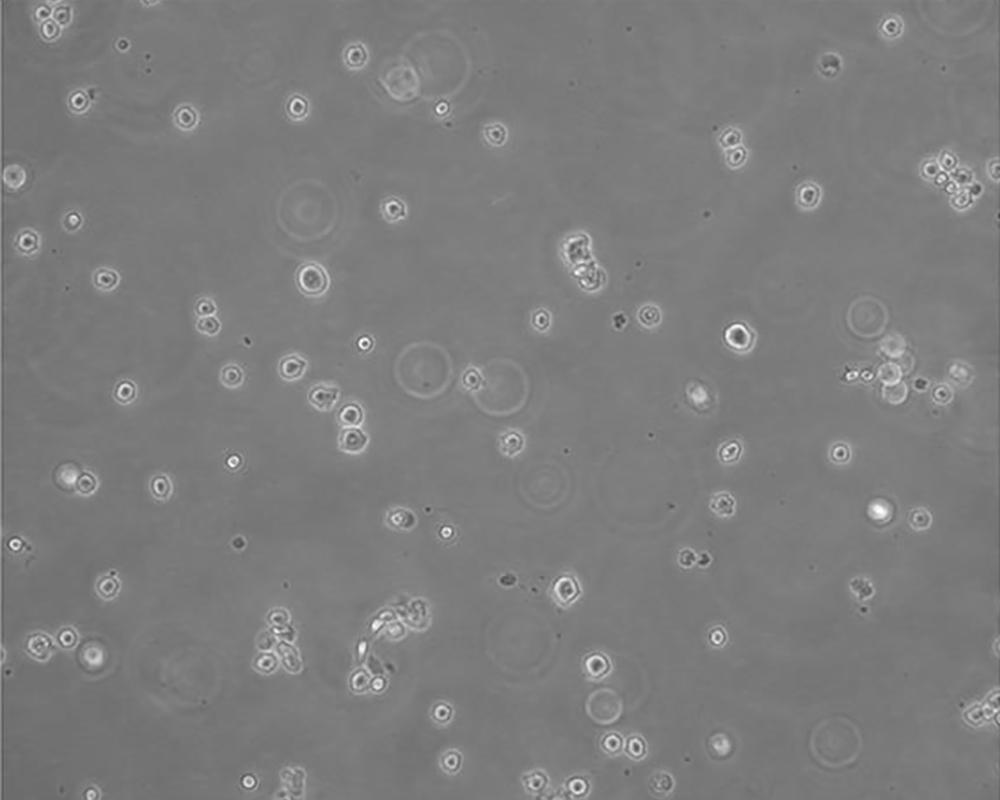

生長特性 suspension

形態(tài)特征 lymphoblast

細胞描述 該細胞來源于多發(fā)性骨髓瘤男性患者,表達IgG,分泌IL-6。